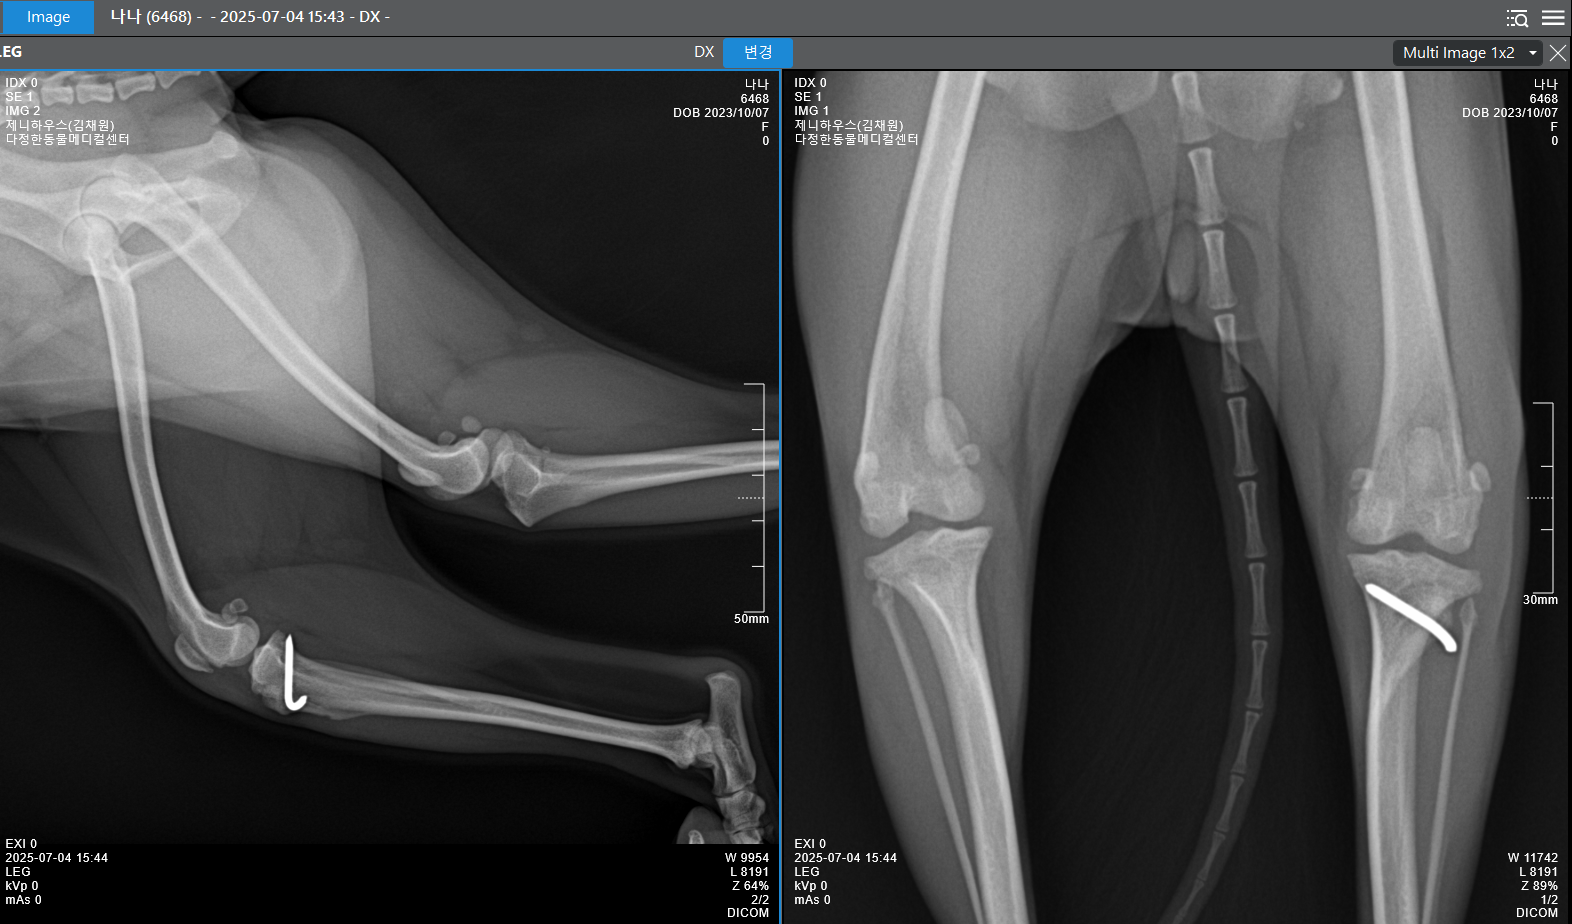

폐 번식장에서 구조된 나나.

당시 나나는 양쪽 후지 슬개골 탈구가 심해서

빠른 수술이 필요했는데,

세종 다정한동물메디컬센터에서

6월 5일 한쪽 슬개골 수술을 진행했습니다.

다른 슬개골은

한 달 뒤에 수술 예정이며,

현재 나나는

꾸준히 정기검진 및 재활 관련 약물을 처방받으며

보살핌을 받으며 건강을 회복 중입니다.